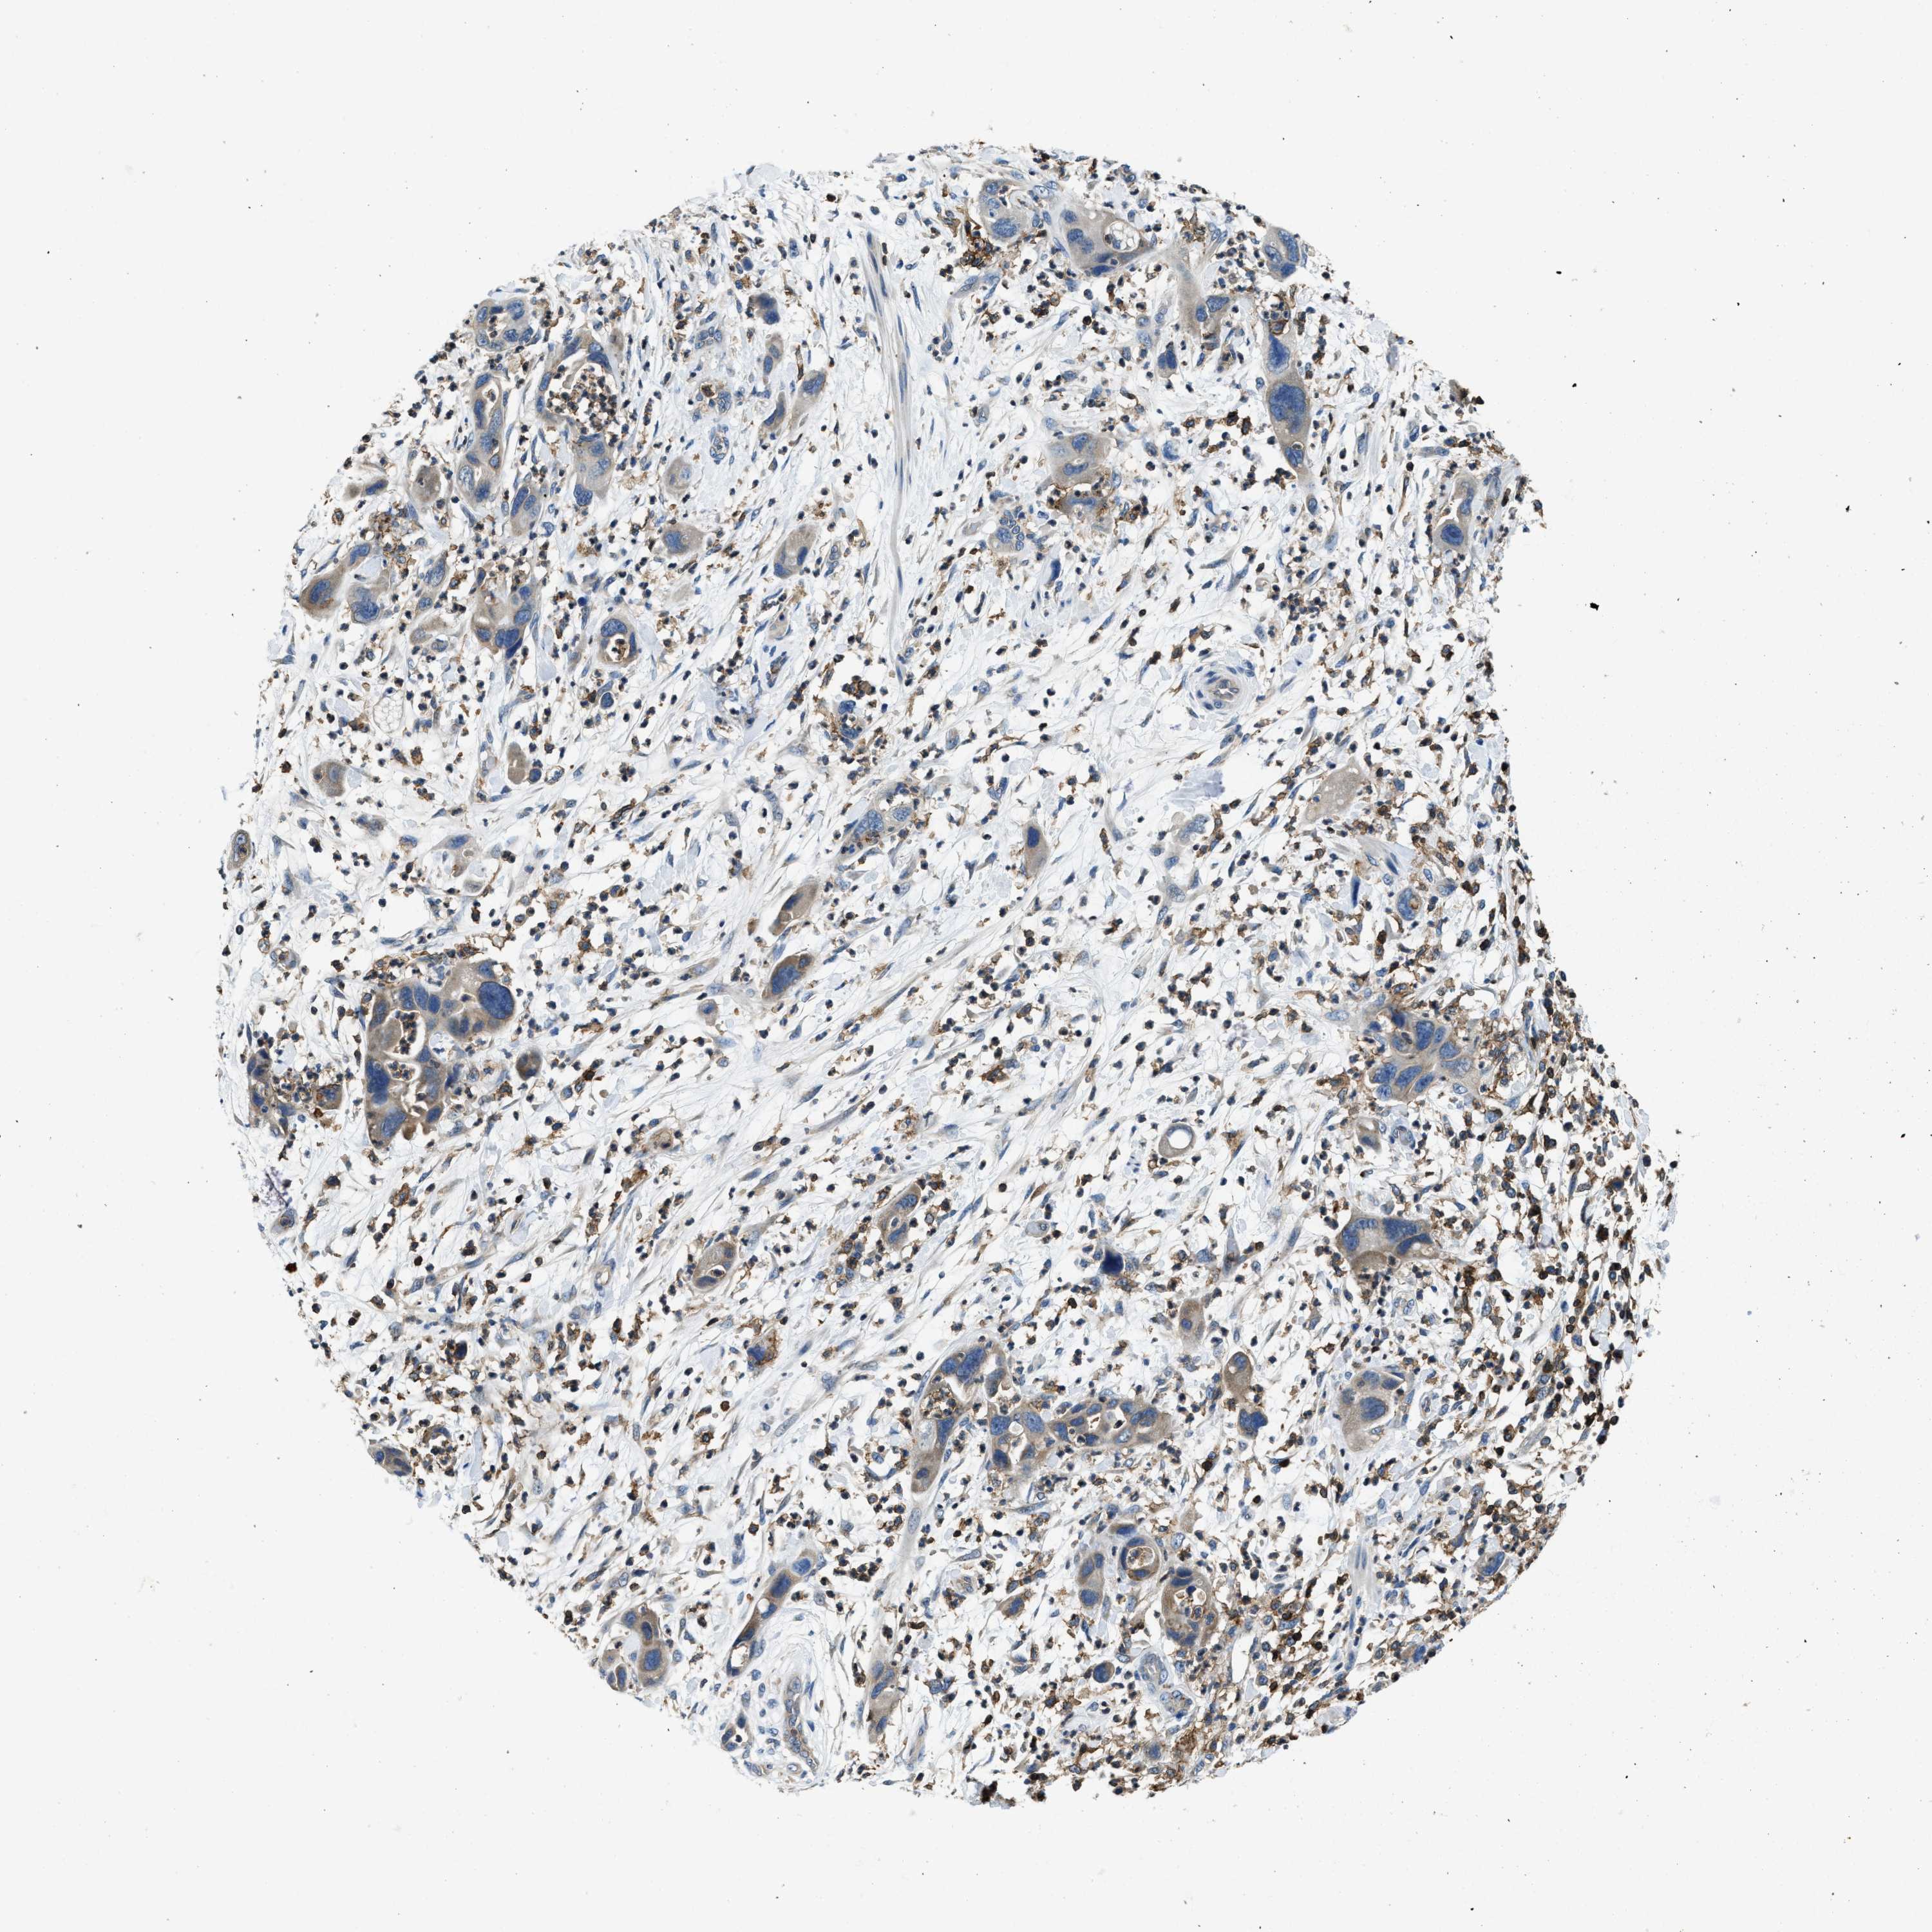

PANCREATIC CANCER - Protein expressioni

A mouse-over function shows sample information and annotation data. Click on an image to view it in a full screen mode. Samples can be filtered based on level of antibody staining by selecting one or several of the following categories: high, medium, low and not detected. The assay and annotation is described here.

Note that samples used for immunohistochemistry by the Human Protein Atlas do not correspond to samples in the TCGA dataset.

Antibody stainingi

Antibody staining in the annotated cell types in the current human tissue is reported as not detected, low, medium, or high, based on conventional immunohistochemistry profiling in selected tissues. This score is based on the combination of the staining intensity and fraction of stained cells.

Each image is clickable and will lead to virtual microscopy that enables deeper exploration of all samples and also displays staining intensity scores, fraction scores and subcellular localization as well as patient and tissue information for each sample.

Antibody HPA021252

Staining

High

Medium

Low

Not detected

Intensity

Strong

Moderate

Weak

Negative

Quantity

>75%

75%-25%

<25%

None

Location

Nuclear

Cytoplasmic/membranous

Cytoplasmic/membranous,nuclear

Adenocarcinoma, NOS